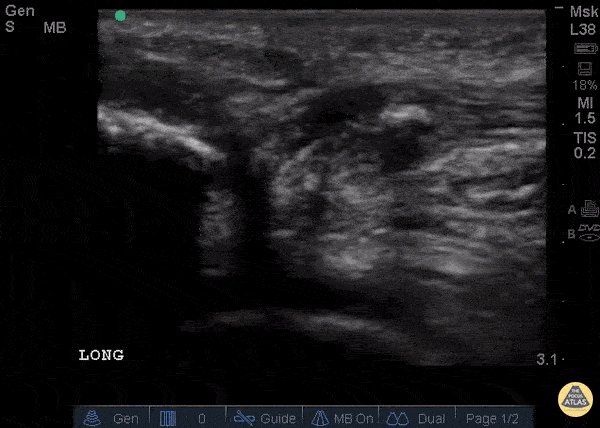

Musculoskeletal - Patellar Tendon Rupture Longitudinal

34 y/o M presented with swelling and pain inferior to his knee following hearing a pop when he jumped playing basketball. Pt unable to extend leg and x-ray demonstrated a high riding patella. Longitudinal ultrasound showed a hyperechoic tendon that is not continuous between the patella and tibia, with an anechoic area of hemorrhage consistent with patellar tendon rupture. Patellar tendon rupture can be diagnosed with H&P and POCUS can be used to confirm this diagnosis. In one study, diagnosis of tendon rupture by physical exam had a sensitivity of 100% and specificity of 76%, while diagnosis by POCUS had a sensitivity of 100% and specificity of 95%. Ultrasound is especially useful in patients who cannot cooperate with a physical exam, and serial ultrasound can also be used to monitor healing of a tendon rupture. Caroline Rago - MS4, Dr’s Bryan Jarrett and Joshua Schechter - Kings County Emergency Medicine